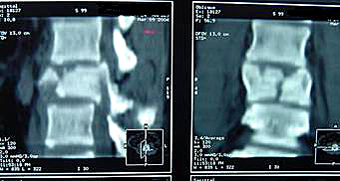

- El segundo tipo en frecuencia es la fractura-estallido. En esta fractura el cuerpo vertebral "estalla" en múltiples fragmentos. Suele ser debida a traumatismos de alta energía y no es infrecuente que se asocie a lesiones neurológicas ya que los fragmentos óseos pueden desplazarse al interior del canal raquídeo y comprimir las estructuras nerviosas. No obstante, la presencia de estos fragmentos dentro del canal no implica necesariamente que se haya producido o vaya a producirse una lesión neurológica.